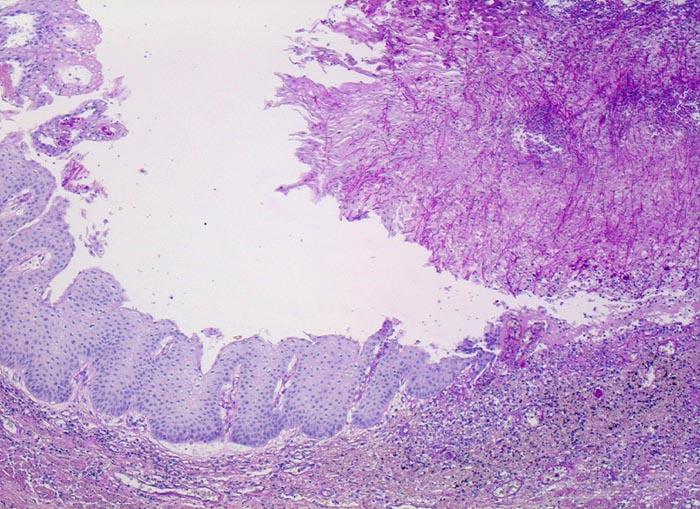

PathoPic – image database / PathoPic ID 5153 - Soorösophagitis

Soorösophagitis

Die Schleimhaut links im Bild ist weitgehend unauffällig. Am rechten Bildrand ist ein Ulkus erkennbar, welches von einem dicken Geflecht aus Pseudohyphen bedeckt wird.

Weisse, streifenförmige Beläge auf der Mucosa

Mann, 75 Jahre, mit bekanntem multiplen Myelom. Autopisepräparat. Progrediente Dysphagie.

Histologie

50